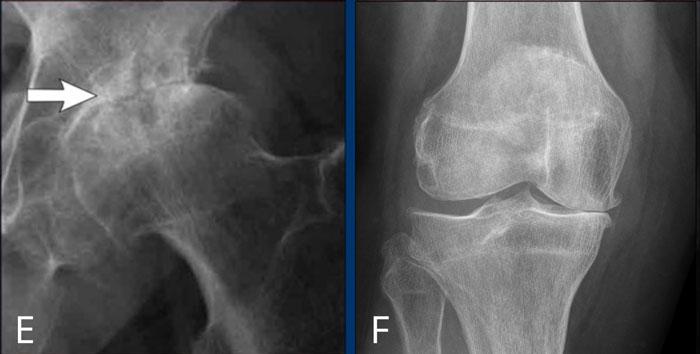

E

Thoái hóa khớp háng

Hẹp nặng khe khớp háng không đồng đều kèm hình thành gai xương, xơ cứng xương dưới sụn và nang xương kích thước lớn.

Ở giai đoạn muộn, có thể xuất hiện biến dạng khớp với hiện tượng mở rộng và biến dạng chỏm xương đùi.

F

Thoái hóa khớp gối

Hẹp khe khớp đùi-chày khoang trong mức độ vừa đến nặng, không đối xứng, kèm hình thành gai xương và xơ cứng xương dưới sụn (phân loại Kellgren-Lawrence độ 3-4).